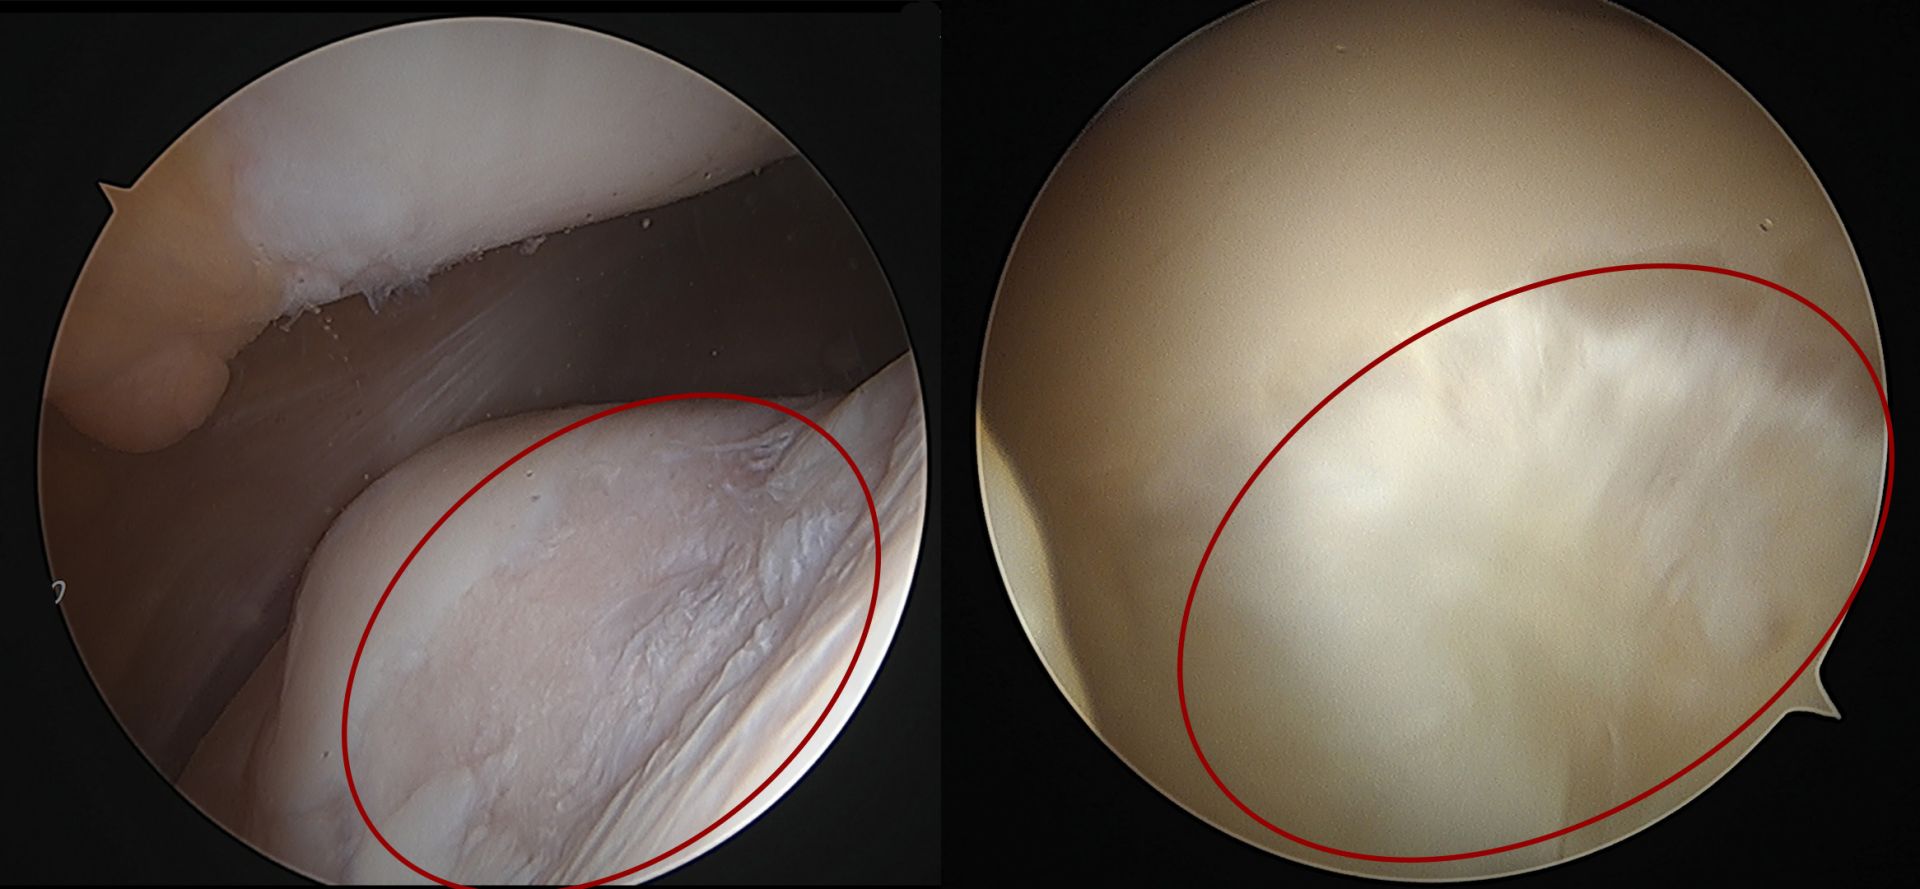

關節鏡頭下膝蓋軟骨損傷情形(左),經自體軟骨移植,成功再生(右)。

女老師決定先接受右膝蓋「自體軟骨移植再生術」,王稚暉醫師指出,這項手術,是先在患者自己未受破損部位取下健康膝蓋軟骨,一個單位約2公克,共取出三個單位,再以特殊器材和技術在已破損的患部鑽三個凹槽,每個凹槽約口0.8公分,將三個單位的健康軟骨一一的種進凹槽,術後一年影像證實,原先膝蓋軟骨破損處已長出健康的軟骨組織,證實了自體軟骨再生技術的成功。